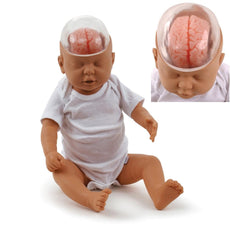

RSD’s Body Section Phantoms provide a comprehensive evaluation of the imaging system and imaging techniques under realistic conditions. They are rugged, easily transported, and shatter-proof.

Available in opaque or transparent, in a natural position or with 90° flexion, RSD’s Elbow Phantoms allow for

tremendous flexibility with teaching and training. With the anatomy and radio fidelity of RSD’s Take-Apart Pixy, our

Elbow Phantoms represent an average male 5 ft. 9 in. tall (175 cm), with a weight of 162 lbs (74 kg). They are

rugged, easily transported, and shatter-proof.

RSD’s Body Sections do not replace simple geometric phantoms that are used to evaluate individual characteristics of

an imaging system. Instead, they provide comprehensive evaluation of the imaging system and imaging techniques under

realistic conditions.

- Bone composed of cortical (TS-1003) and trabecular bone (TS-1002) equivalent materials

- Foot encapsulated in RSD soft tissue material (TS-1001-T)

- Additional soft material made of soft tissue material with density of 1.1 g/cc